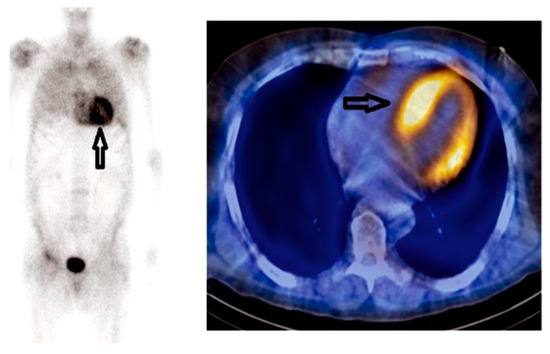

The role of 99mTc-YP/DPD/HMDP cardiac scintigraphy was highlighted in the recently developed consensus algorithm for the non-invasive diagnosis of CA (Figure 6) [47].

Figure 6.

Consensus algorithm for non-invasive diagnosis of cardiac amyloidosis.

This algorithm gives an approach to the evaluation of patients with CA considering the probability of CA. The diagnosis of ATTR-CA can be highly suspected, avoiding the need for endomyocardial biopsy, if there are not clonal abnormalities and there is a high level of uptake of 99mTc-PYP/DPD/HMDP in the radionuclide imaging.

On the other side, patients with biomarker abnormalities, such as high light chain levels in serum/urine immunofixation, have a high probability of AL-CA, and they should be evaluated by hematologists. Cardiac involvement can be evaluated with the aforementioned non-invasive imaging techniques or with endomyocardial biopsy.